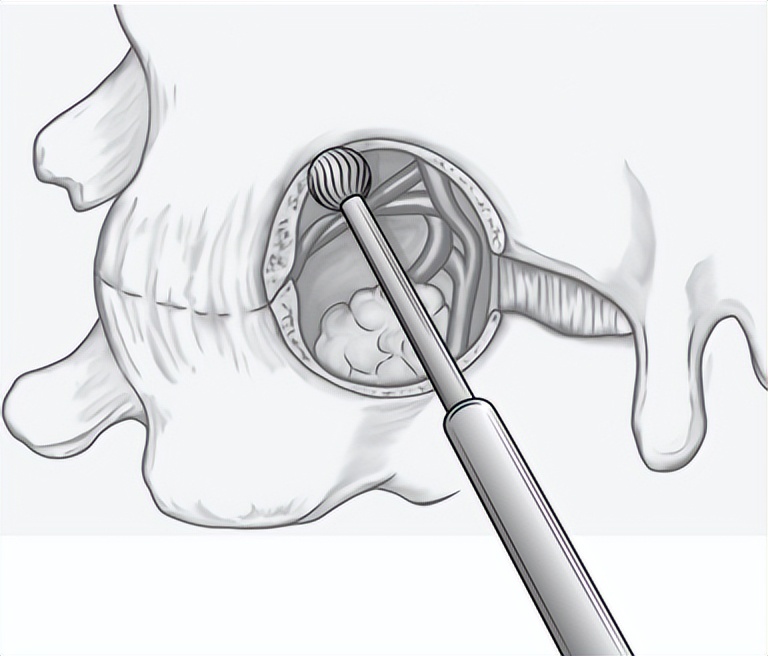

keyhole手术示意图

颈椎后路keyhole手术,即脊柱内镜下后路颈椎椎间孔切开术,无需经过前方诸多重要组织结构,通过内镜的通道在颈椎后方运用“钥匙孔”技术从椎间孔后“开门”进入,不切除棘突,不破坏椎板和椎间盘之间结构,对颈椎后方韧带复合体损伤较小,降低了软组织剥离等相关并发症的发生率,提高了在敏感的神经结构周围实施手术的安全性。